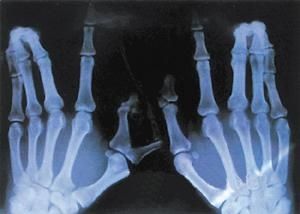

1. 佝僂?。撼0l(fā)生在日照不足、喂養(yǎng)不當的嬰兒以及出生后生長較快的早產兒。典型的骨骼畸形表現(xiàn)為方頭、雞胸、漏斗胸、念珠肋、O 型腿和 X 型腿等,一般多見于 6 個月以內嬰兒。

8. 自身免疫疾?。后w內維生素 D 含量水平與類風濕性關節(jié)炎的發(fā)生發(fā)展關系密切,適當的補充維生素 D 可使患自身免疫性疾病的風險下降,長期適量的補充維生素 D 有助于預防自身免疫疾病。